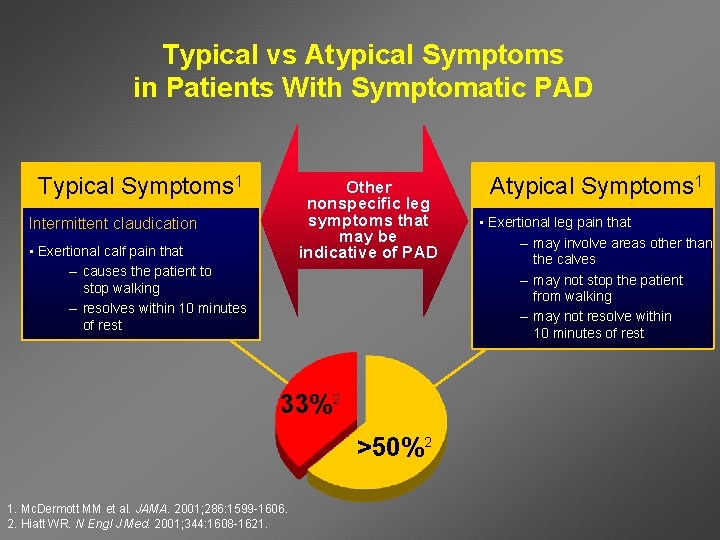

Typical vs Atypical Symptoms in Patients With Symptomatic PAD Typical Symptoms 1 Other nonspecific leg symptoms that may be indicative of PAD Intermittent claudication • Exertional calf pain that – causes the patient to stop walking – resolves within 10 minutes of rest 33%2 >50%2 1. Mc. Dermott MM et al. JAMA. 2001; 286: 1599 -1606. 2. Hiatt WR. N Engl J Med. 2001; 344: 1608 -1621. Atypical Symptoms 1 • Exertional leg pain that – may involve areas other than the calves – may not stop the patient from walking – may not resolve within 10 minutes of rest